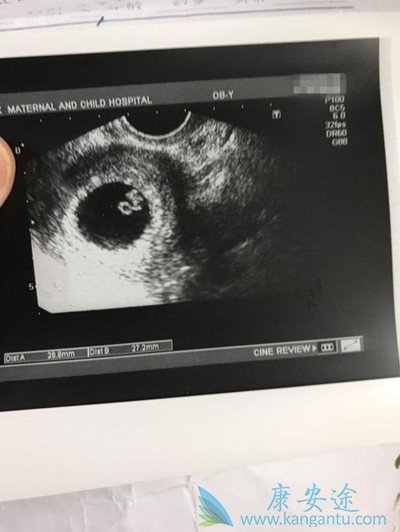

等到第10天又去医院检查,医生说宝宝暂时正常。等到第30天左右的时候,小腹有一点点胀痛,老公生怕出什么问题,紧张着又跑去医院,医生安慰我们说宝宝有胎心胎芽,一切都挺好的。我们这才放下心来,真是幸福到哭!